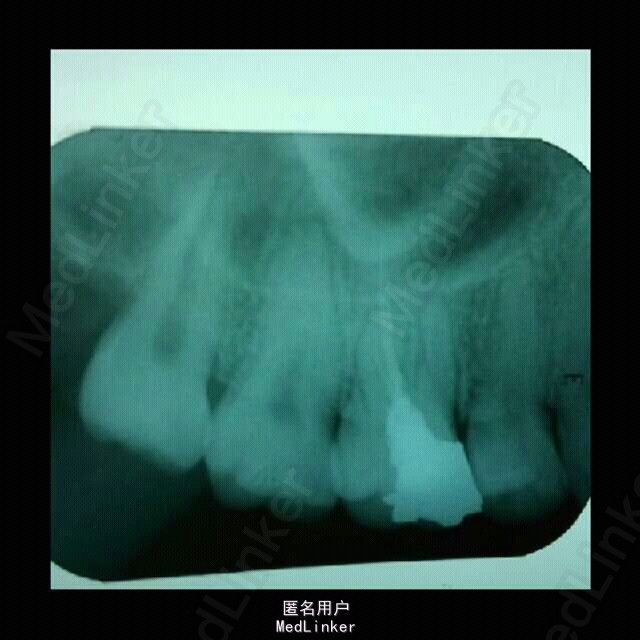

病人之前在其他地方根管治疗后打了纤维桩,有根管遗漏了,现在重新做,晒一下治疗过程。